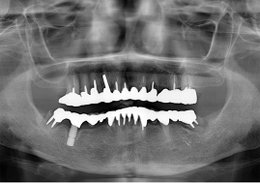

下顎のALL-ON-4①(下の歯のオールオンフォー)

-

- 治療内容

- 下顎右側に以前埋入したインプラントの撤去を行い、歯周病の進行が著しかった残存歯の抜歯を行うと同時にインプラントの埋入を行い、当日仮歯を装着した

- 治療費用

- 下顎ALL-ON-4:4,000,000円(税別)

- 治療期間

- 6ヶ月